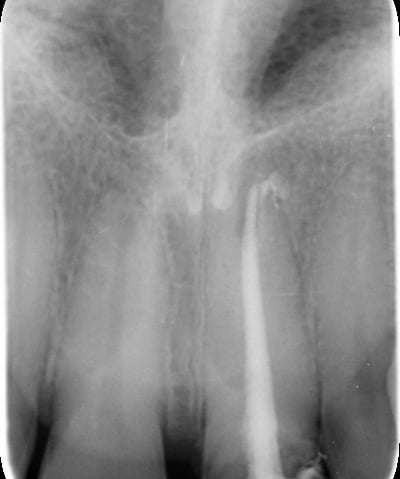

1. Ritrattamento endodontico:

Il primo passo è stato rimuovere la vecchia otturazione canalare e ritrattare i canali radicolari, assicurando una pulizia accurata e la successiva otturazione tridimensionale per prevenire future complicanze.